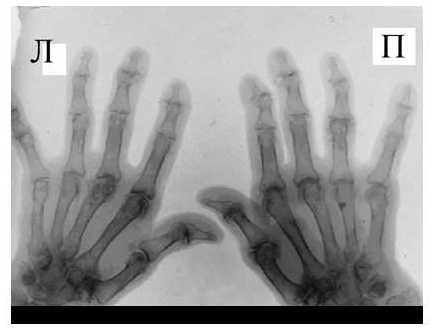

Для псориатического артрита, также поражающего мелкие суставы кистей, отличительным признаком от РА является отсутствие стадийности, поражение суставов, как правило, несимметрично, частые проявления артрита без околосуставного остеопороза, являющегося патогномоничным для РА. Изолированное поражение дистальных межфаланговых суставов кистей при отсутствии изменений в других мелких суставах кистей, осевое поражение 3-х суставов одного пальца.

Рис. 5 Множественный остеолиз и деструкции эпифизов костей с разнонаправленными деформациями суставов при псориатическом артрите.

При развернутой картине болезни деструкция концевых фаланг (акроостеолиз) и чашеобразная деформация проксимальной части фаланг пальцев кистей вместе с концевым сужением дистальных эпифизов симптом «карандаш в колпачке» (рис. 5), множественный остеолиз и деструкции эпифизов костей с разнонаправленными деформациями суставов (мутилирующий артрит).